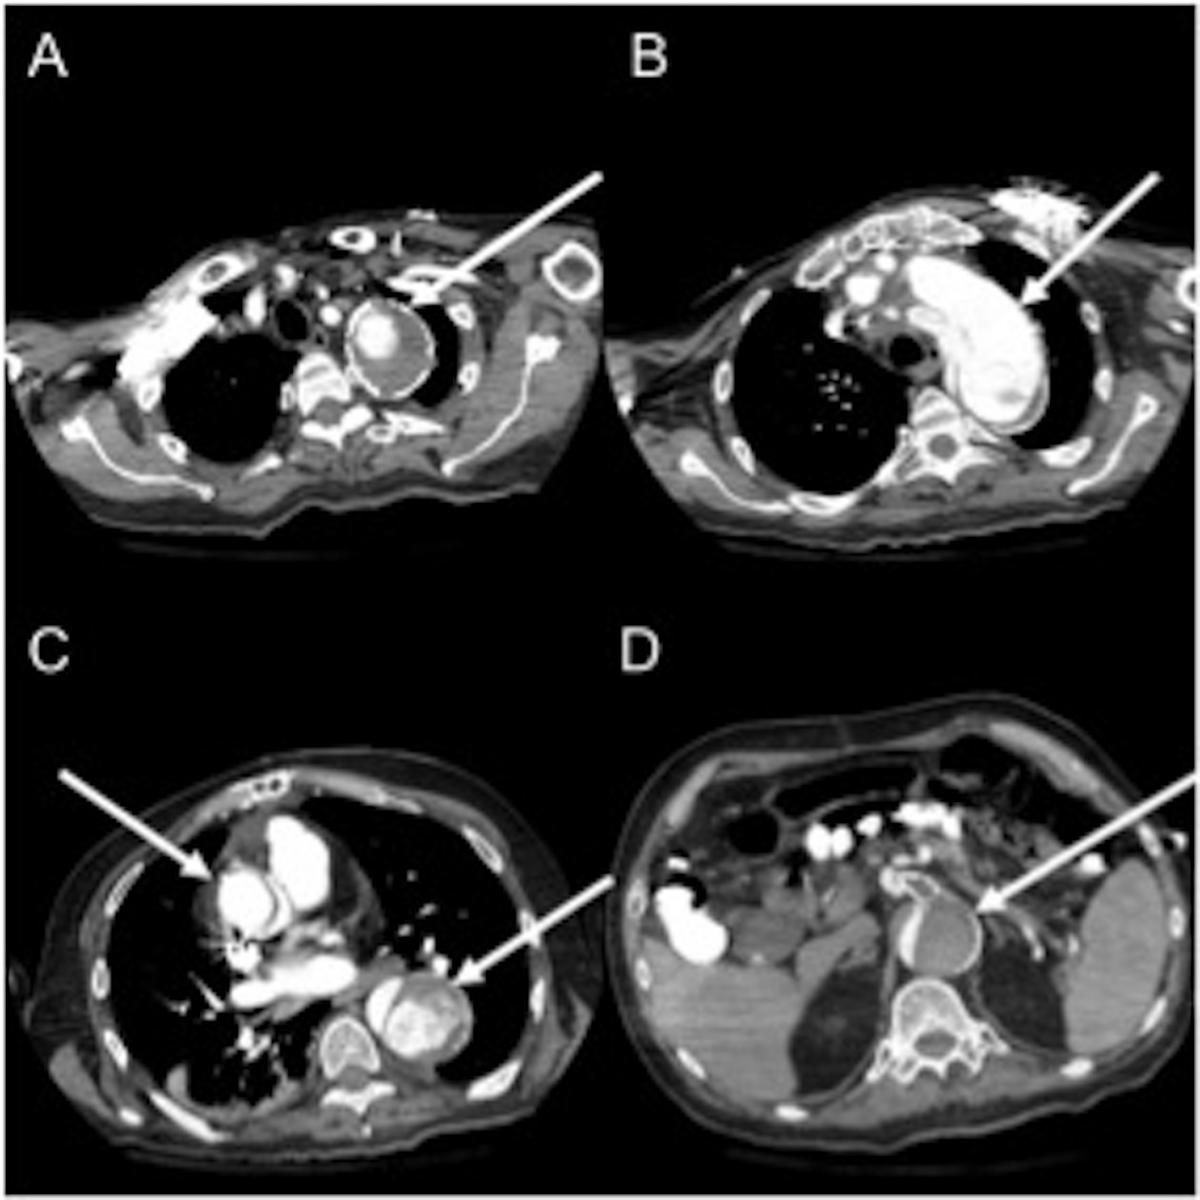

A 60-year-old male presented with chest pain, underwent a CT angiogram in the emergency department, demonstrating a 6.5 cm proximal ascending and transverse aorta and 7.5 cm descending aorta due to chronic aortic dissection (Figure 1,2). His medical co-morbidities included hypertension, previous stroke, coronary artery disease, sick sinus syndrome, cardiomyopathy, and dyslipidemia. His surgical history was positive for four open-heart operations, including: aortic valve replacement, Bentall- Cabrol operation for type A dissection, reoperation for delayed hemorrhage from suture-line pseudoaneurysm, and coronary artery bypass grafting.

This extensive surgical history turned out to be life-saving for this patient. The preoperative CT scan also showed a contained rupture of an ascending pseudoaneurysm into the retro-aortic space (Figure 1C). Given his extensive adhesions, he did not develop frank rupture or tamponade physiology and the area of extravasation was contained by previous adhesions.

Figure 1: CT angiogram showing the thoracic aortic aneurysm. A: Aortic arch aneurysm with contrast enhanced true lumen surrounded by thrombus. B: Aortic arch with proximal septum. C: ascending aorta with contained rupture of a pseudoaneurysm in the retro-aortic space. D: Infrarenal abdominal aortic dissection with clotted false lumen.